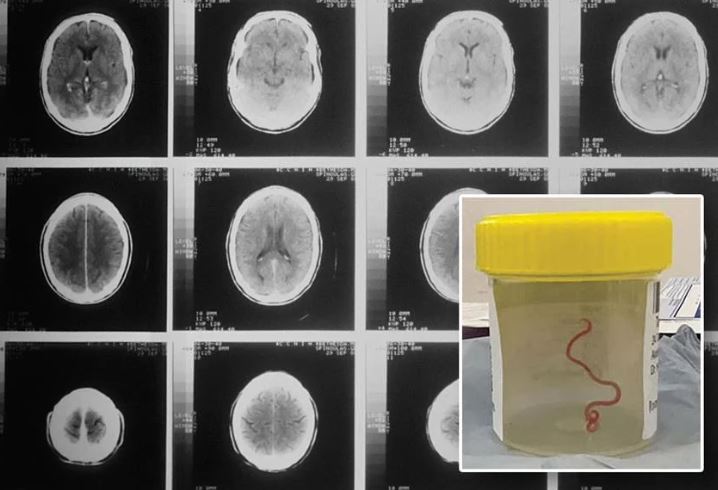

Η νευροχειρουργός, η Δρ Hari Priya Bandi, είχε βγάλει ένα παρασιτικό σκουλήκι μήκους 8 εκατοστών από την ασθενή της, γεγονός που την ώθησε να καλέσει τον Senanayake και άλλους συναδέλφους του νοσοκομείου για συμβουλές σχετικά με το τι έπρεπε να κάνει στη συνέχεια.

Μέχρι το 2022, τα συμπτώματά της περιλάμβαναν επίσης λήθη και κατάθλιψη, με αποτέλεσμα να παραπεμφθεί σε νοσοκομείο της Καμπέρα. Μια μαγνητική τομογραφία του εγκεφάλου της αποκάλυψε ανωμαλίες που απαιτούσαν χειρουργική επέμβαση.

«Η Καμπέρα είναι ένα μικρό μέρος, οπότε στείλαμε το σκουλήκι, το οποίο ήταν ακόμη ζωντανό, κατευθείαν στο εργαστήριο ενός επιστήμονα του CSIRO, ο οποίος έχει μεγάλη εμπειρία με τα παράσιτα», δήλωσε ο Senanayake. «Απλώς το κοίταξε και είπε: ‘Θεέ μου, αυτό είναι το Ophidascaris robertsi’».

Το Ophidascaris robertsi είναι ένα στρογγυλό σκουλήκι που συναντάται συνήθως στους πύθωνες. Ο ασθενής του νοσοκομείου της Καμπέρα σηματοδοτεί την πρώτη παγκοσμίως περίπτωση του παρασίτου που βρέθηκε σε ανθρώπους.